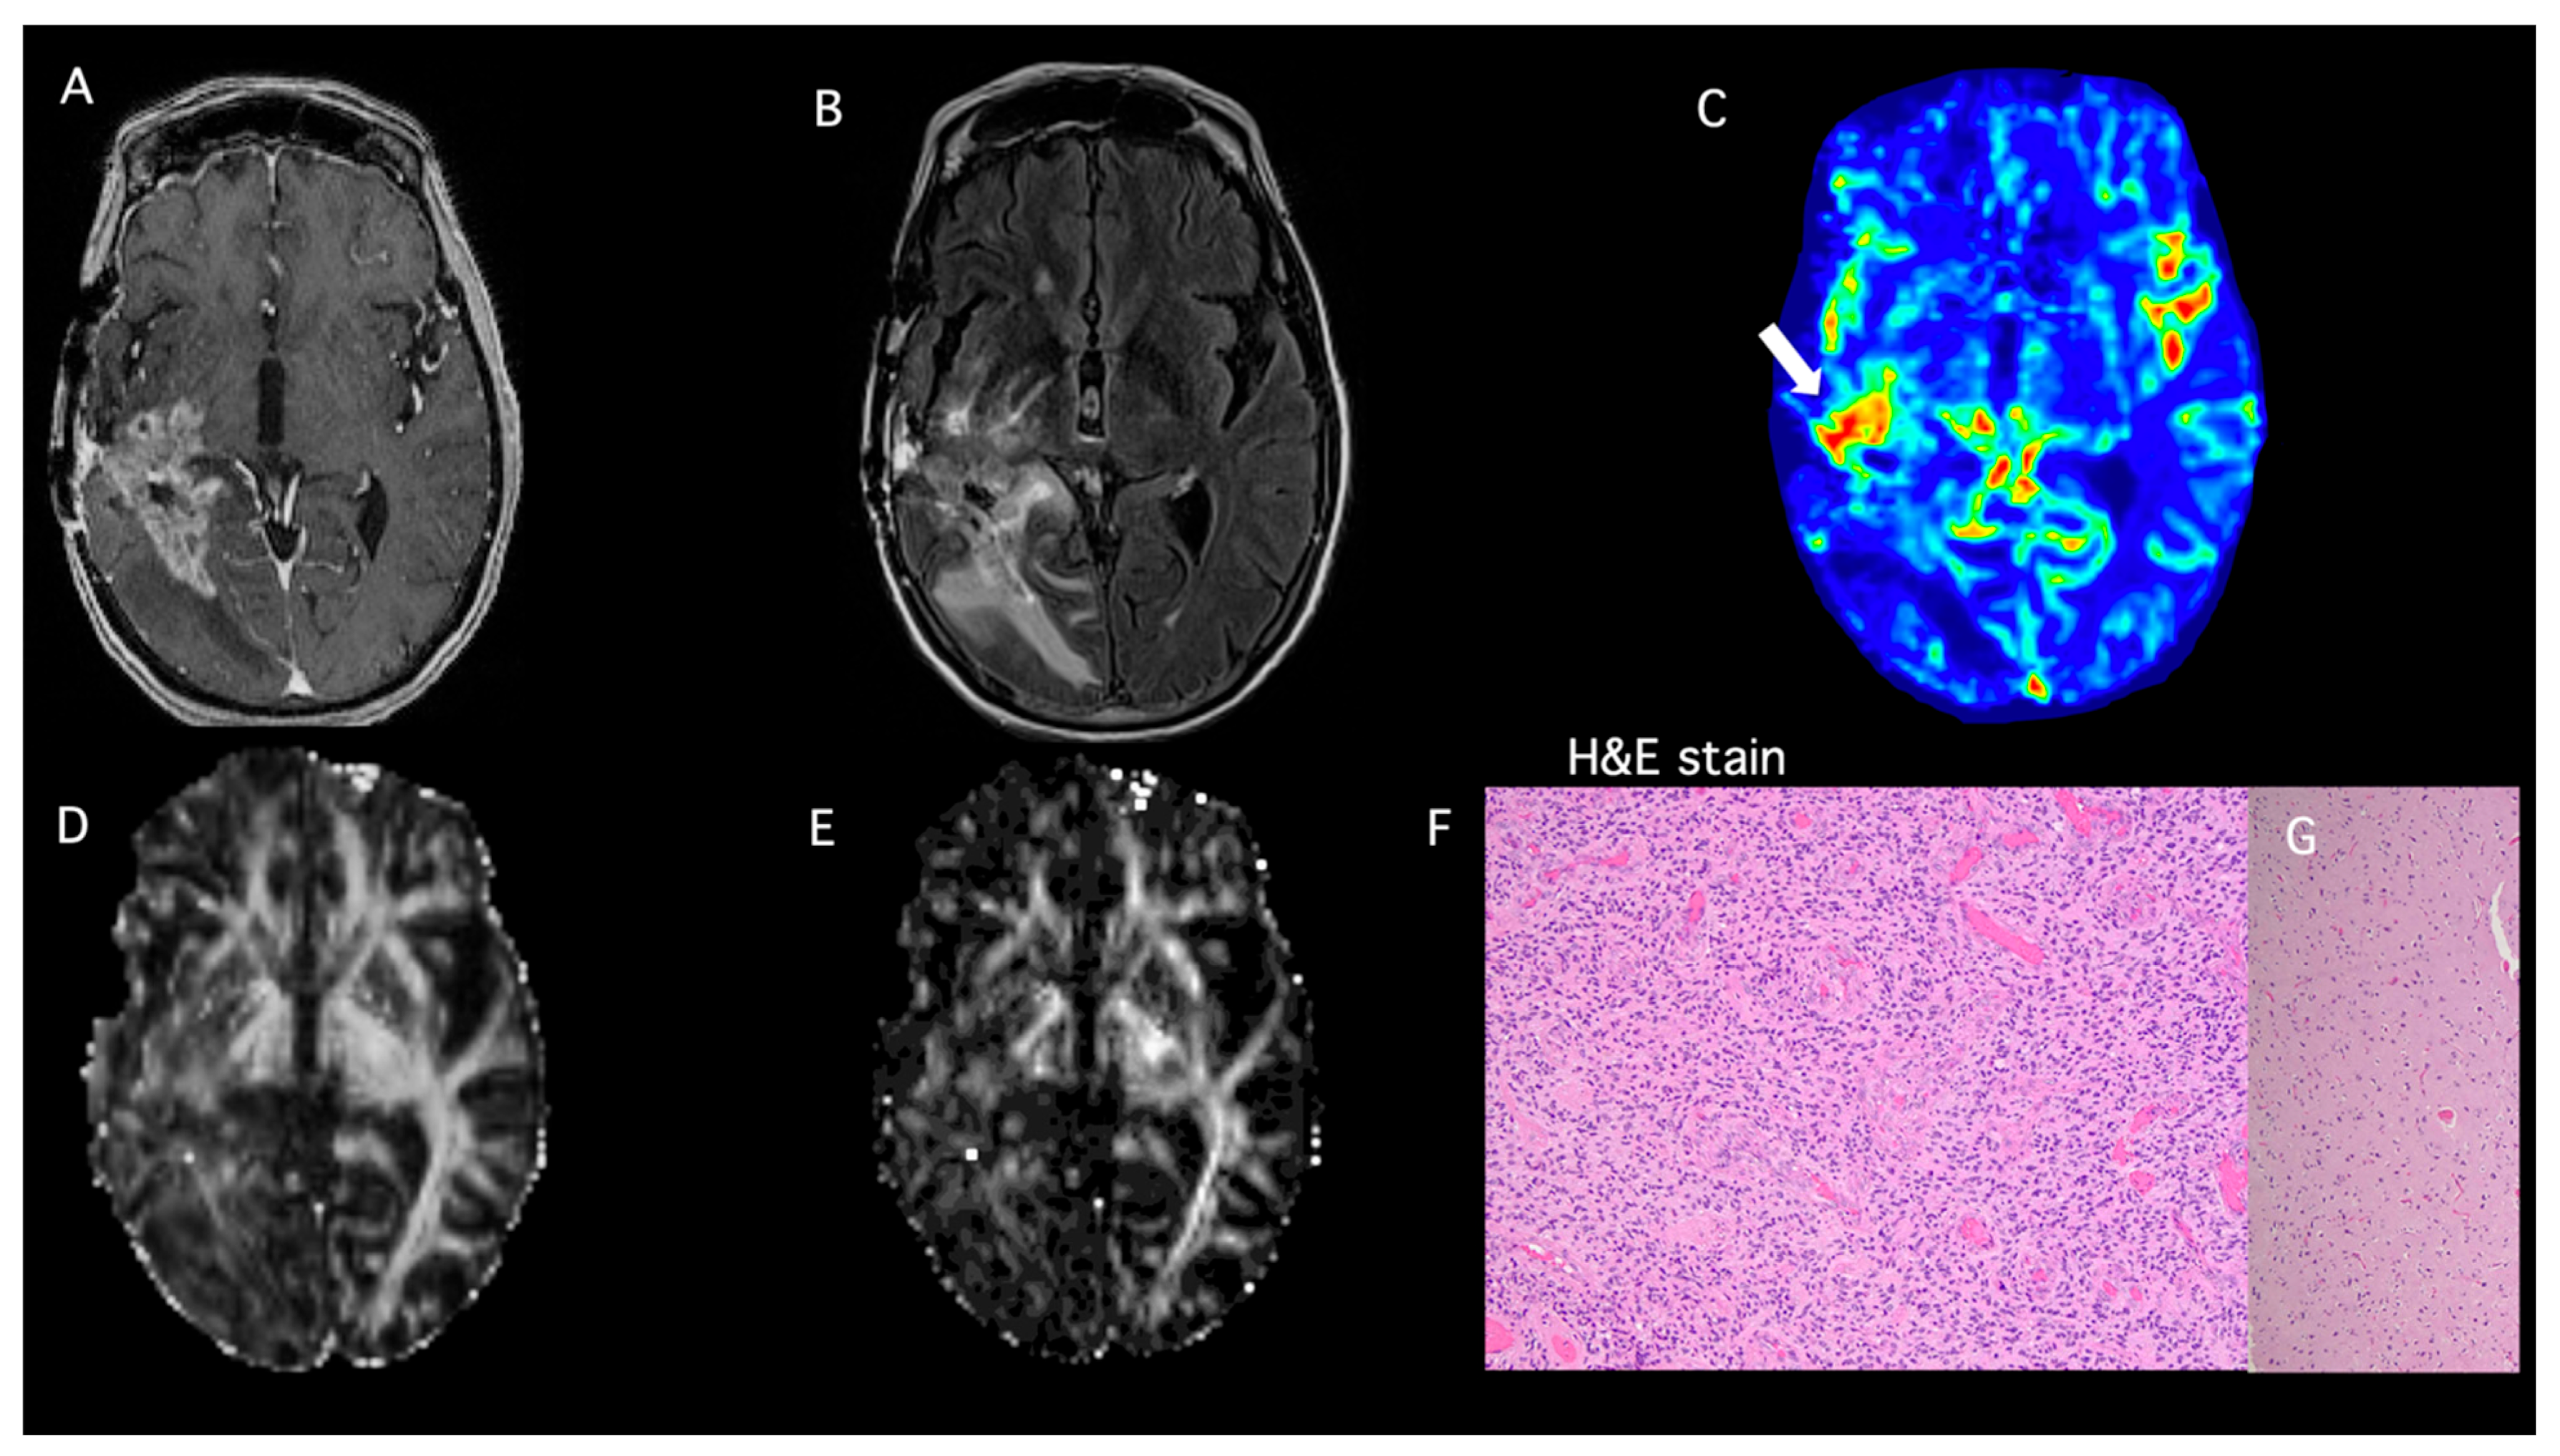

- Patient 1

| Patient ID | DTI-FA | DTI-CL | DSC-rCBVmax | PP-Value TP ≥ 50% PsP < 50% | Histopathology | Modified RANO |

|---|---|---|---|---|---|---|

| 1 | 0.09 | 0.03 | 1.6 | 1% | PsP | |